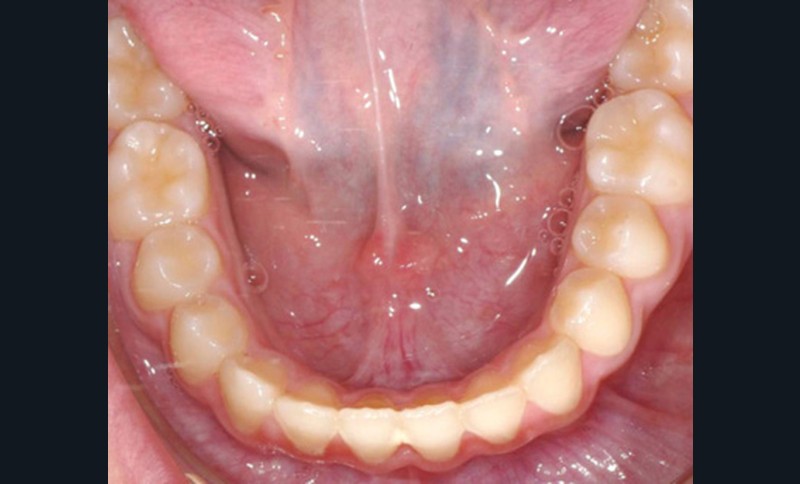

Cette patiente a été suivie dans le cadre d’un traitement interceptif alors qu’elle avait 9 ans. Elle présentait une endognathie maxillaire et une béance antérieure importante liées à des troubles fonctionnels évidents. En effet, l’examen clinique révélait une ventilation buccale exclusive, des ronflements nocturnes et une déglutition atypique. Nous avions noté à l’époque un manque de place pour l’évolution des dents définitives et un inversé d’articulé bilatéral. Les parents avaient rencontré un médecin ORL, mais avaient refusé une intervention visant à enlever les amygdales. Les deux canines maxillaires étaient incluses (fig. 1 à 6).

Quelques années plus tard, au moment de démarrer sa prise en charge orthodontique, la patiente présentait à nouveau une béance antérieure, un décalage des milieux incisifs de 2 mm et le problème transversal avait récidivé. Lors de l’examen clinique, elle présentait un inversé d’occlusion bilatéral postérieur et une ventilation buccale exclusive. À la suite du refus de réaliser l’amygdalectomie de façon précoce, elle ronflait toujours et sa déglutition ne s’était pas modifiée malgré des séances d’orthophonie (fig. 7 à 15).